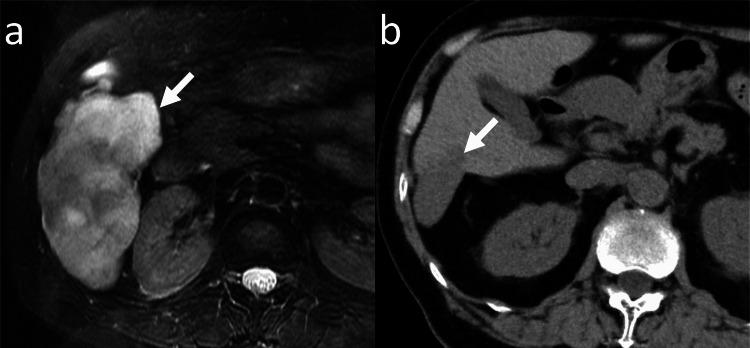

Computed tomography (CT) and magnetic resonance imaging (MRI) reports at Kyoto University Hospital, Kyoto, Japan, between January 2001 and March 2023 were retrospectively searched to find adult patients with hepatic hemangiomas >10 cm. Patients who were followed up without treatment for over six months were included. The maximum diameter of the hepatic hemangioma was compared between the baseline and the final CT or MRI. The clinical course of the patients was evaluated.

Twenty-two patients (17 women, five men; median age, 51 years) were identified. The median diameter of hepatic hemangiomas in the baseline study was 114 mm. Two patients had abdominal distention at the time of the baseline imaging, whereas the others were asymptomatic. After follow-up without treatment (the median; 95.5 months), enlargement, no change, shrinkage of hepatic hemangioma was observed in six, 11, and five patients, respectively. The median growth rate of hepatic hemangiomas was 2.5 mm/year. Two patients underwent liver resection for hepatic hemangioma, while the others were followed up without treatment. In four patients, symptoms appeared or worsened. Two patients died: one patient died from prostate cancer progression; the cause of death for the other was not confirmed.